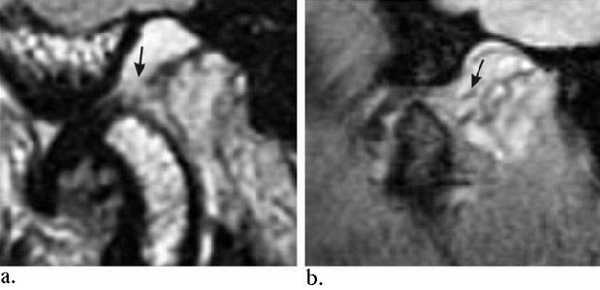

Перемежающийся (вправляемый) вывих /подвывих.

А. Закрытый рот. Переднее смещение диска.

Б. Рот открыт. Диск вернулся в нормальное положение между мыщелком и височной костью.

Фиксированный (невправляемый) вывих.

А. Рот закрыт. Переднее смещение диска.

Б. Рот открыт. Диск продолжает оставаться смещенным.